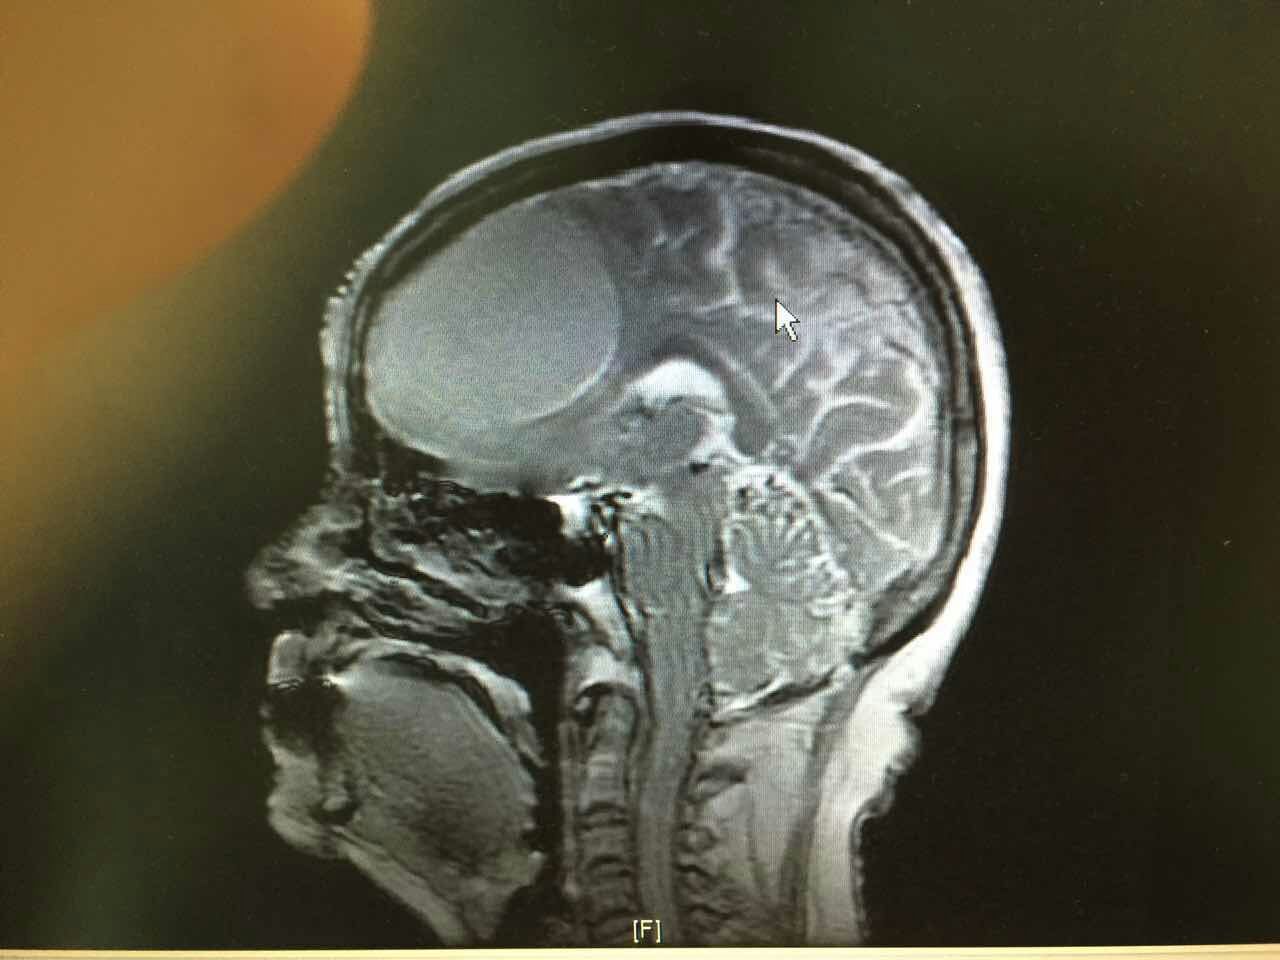

颅内肿瘤等你分析读片专栏1062期

图片尺寸1080x1096